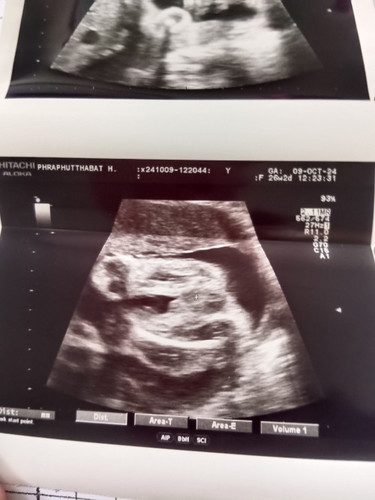

แม่ๆช่วยดูหน่อยค่ะแบบนี้ชายหรือหญิงคะ

เห็นหมอบอกว่าถ้าผู้หญิงมองใบซาวน์ยังไงก็จะคล้ายๆแฮมเบอร์เกอร์ ส่วนผู้ชายจะโด่เด่เลยค่ะบ้านนี้ได้ผู้ชายโด่เด่ให้เห็นตั้งแต่13weekเลย

น่าจะเป็นชายค่ะดูเหมือนเป็นไข่แล้วมีจู๋ยื่นออกมาเหมือนของเราที่ไปซาวด์ดูเพศมา

ผู้ชายค่ะ ภาพคล้ายๆกับบ้านนี้ไข่ใหญ่🤣 บ้านนี้อ้าให้เลยค่ะ🥰

เหมือนผช.เลยค่ะ มีอัณฑะกับจู๋น้อยๆโผล่มานิดนึง

เหมือนจะเป็นญนะค่ะ เห็นเหมือนกลีบน้องค่ะ🥰

ผู้ชายค่ะ น้อนมีไข่เหมือนบ้านนี้เลยค่ะ😅

เหมือนผช.นะคะ เหมือนน้องนั่งทับอ่ะค่ะ

น่าชายนะคะเหมือนเห็นงวงน้อง😅

เหมือนลูกชายเลยค่ะ

ผู้ชายจ้า ภาพชัดมาก 😅